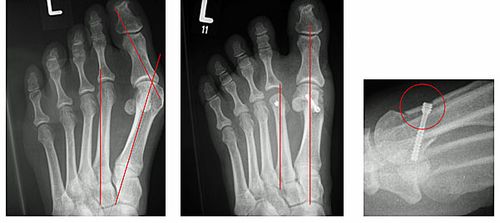

Abb.2: Korrektur einer leichten Hallux valgus Fehlstellung durch eine Chevron Osteotomie (Distale Metatarsale I Osteotomie) mit versenkter Schraube. Der Vorfuß wurde verschmälert und die Knochenachsen begradigt.

Abb.3: a Korrektur einer mittelschweren Hallux valgus Fehlstellung durch eine Basisosteotomie.

b Korrektur einer schweren Hallux valgus Fehlstellung mit luxierten Krallenzehen und chronischer Metatarsalgie durch eine Lapidus Arthrodese. Mit dieser Technik können selbst hochgradige Fehlstellungen begradigt werden. Bei beiden Techniken wird der Knochen wird mit einer winkelstabilen Platte fixiert. Dies bietet ein höchstes Maß an Stabilität und ermöglicht die sofortige postoperative Belastung.